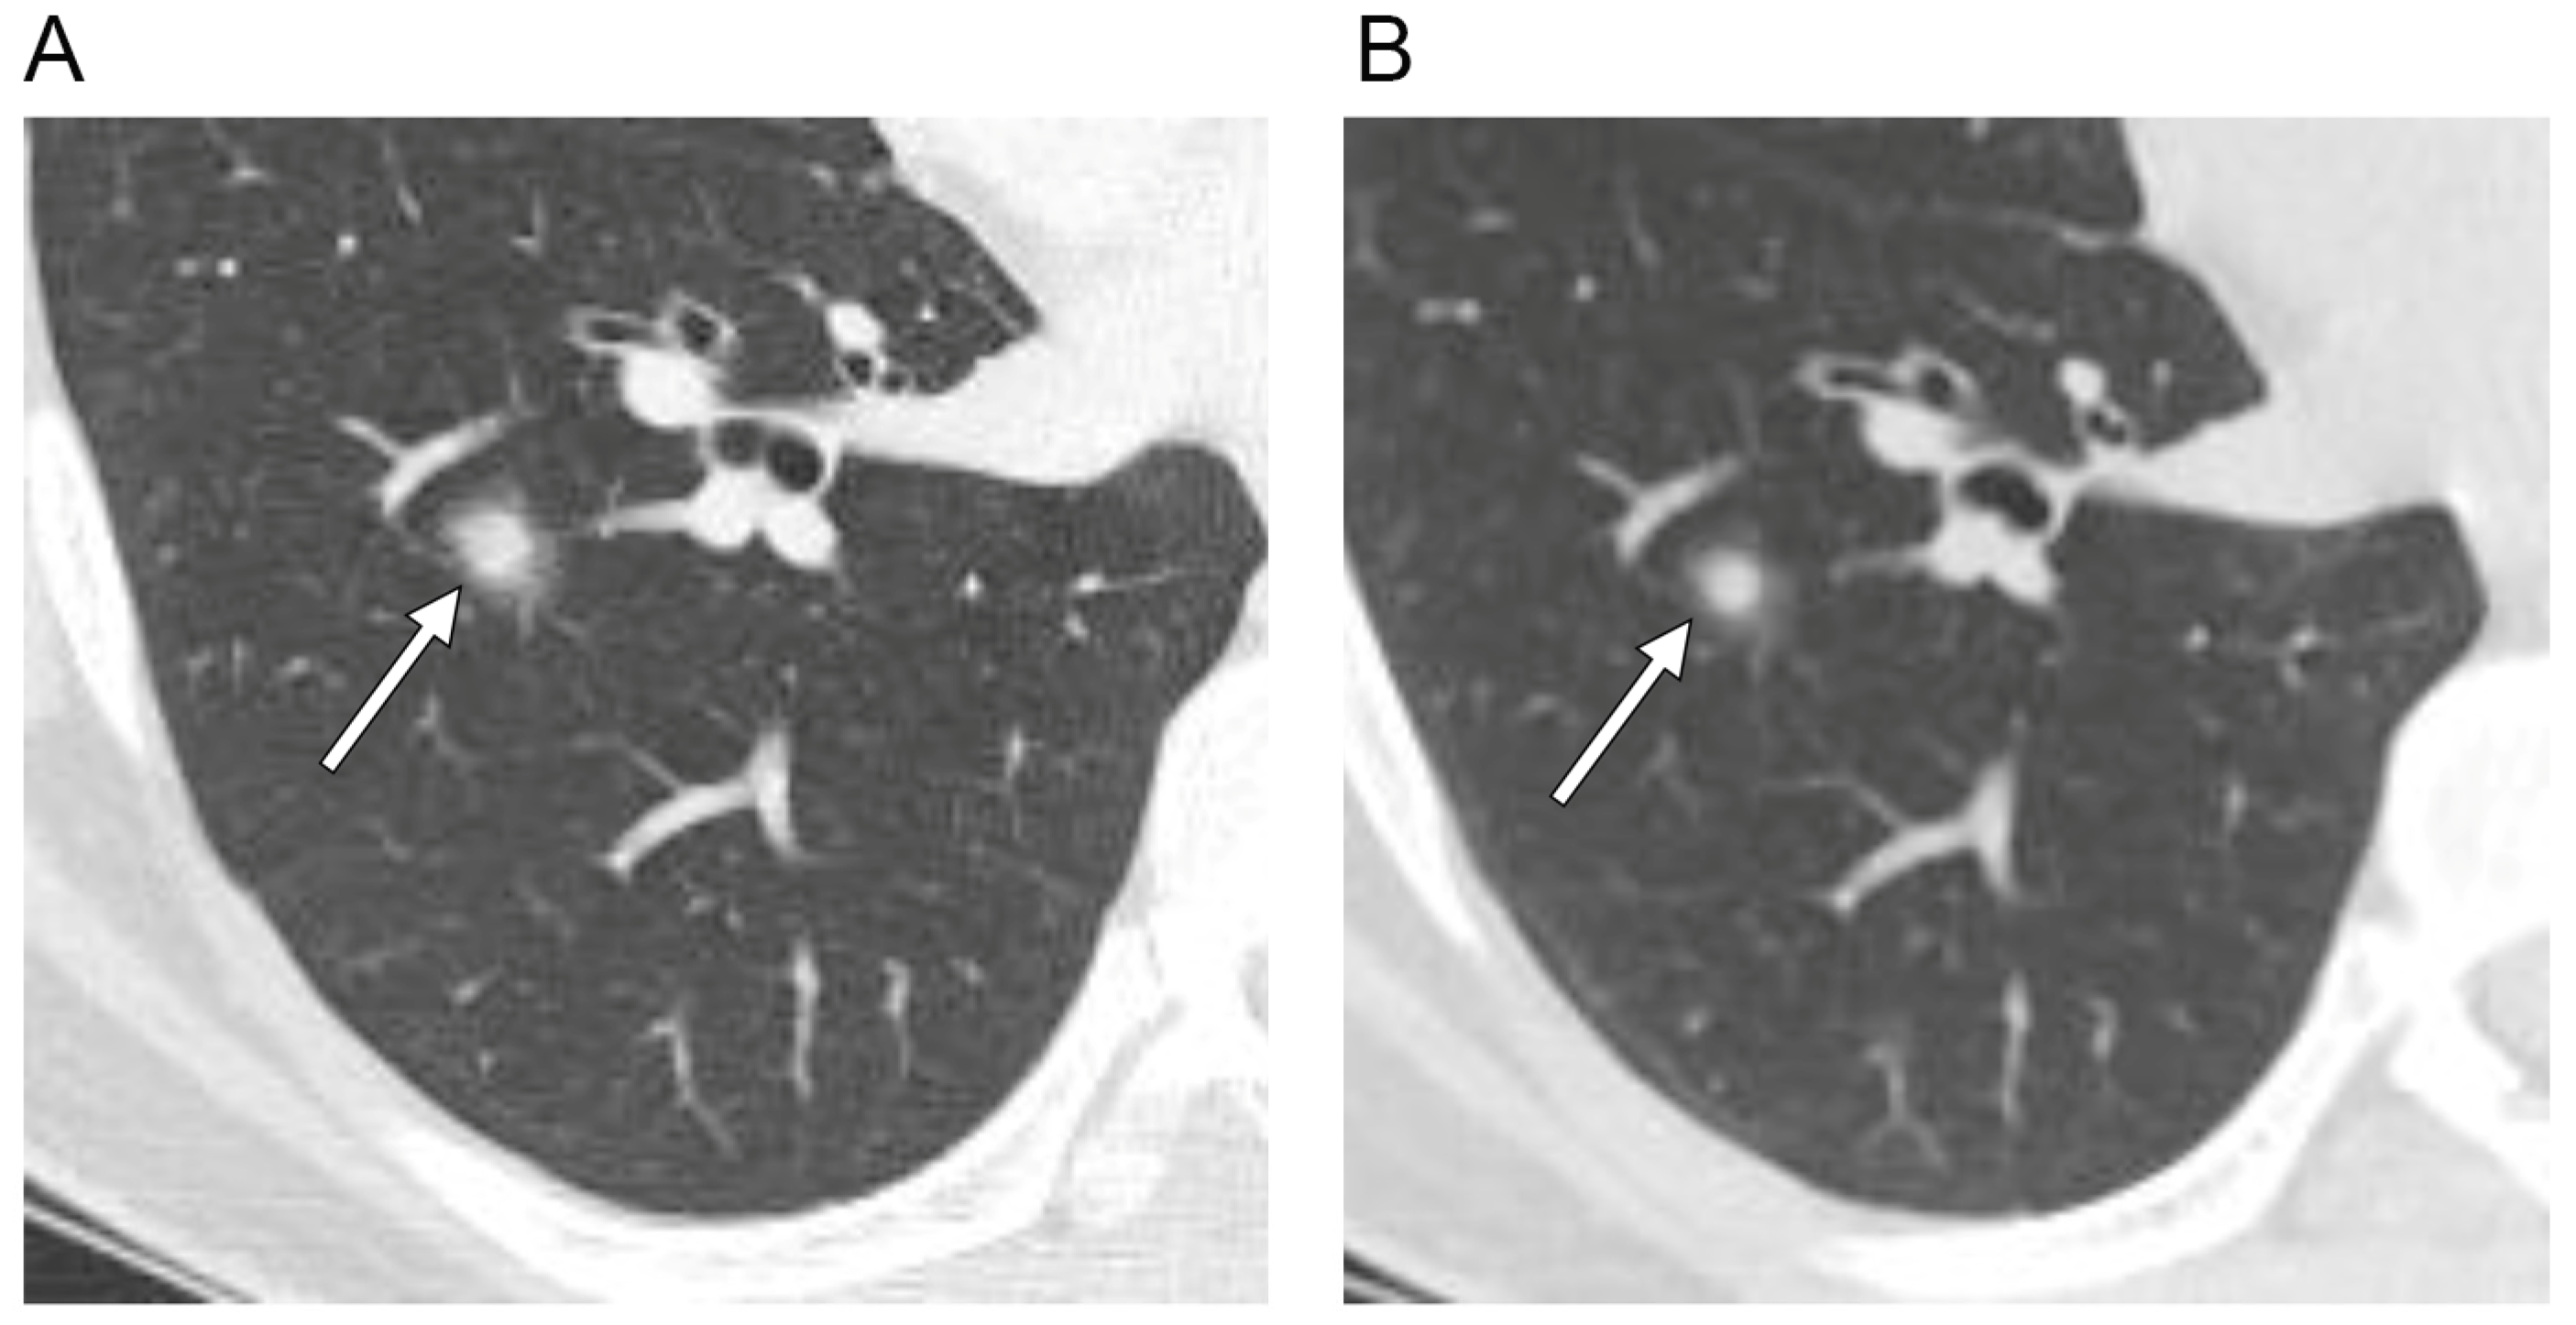

| Change during follow-up period | |

| None | 10 (59) |

| Decrease in size/density or fluctuation in size/shape/density | 3 (18) |

| Increase in size/density | 4 (24) |